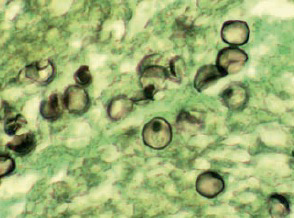

- Cryptococcus neoformans (新型隱球菌)

- 腦膜炎

- 小心鴿子